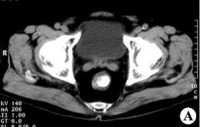

精囊腺(seminal vesicle)CT解剖:精囊位于前列腺上方,膀胱之后、呈对称性卵圆形,与膀胱后下壁间有脂肪组织间隔,仰卧圆形,与膀胱后下壁间有脂肪组织间隔,仰卧时此间隙形成膀胱精囊角,约30度左右,俯卧位时精囊紧贴膀胱,此角消

失。故在判断膀胱或前列腺肿瘤有无侵及精囊时,应取仰卧位以观察此间是否存在和对称。CT上精囊表现为前列腺以上层面膀胱后方对称性的长椭圆形软组织影,CT值35-75Hu不等,双侧共长60mm左右。